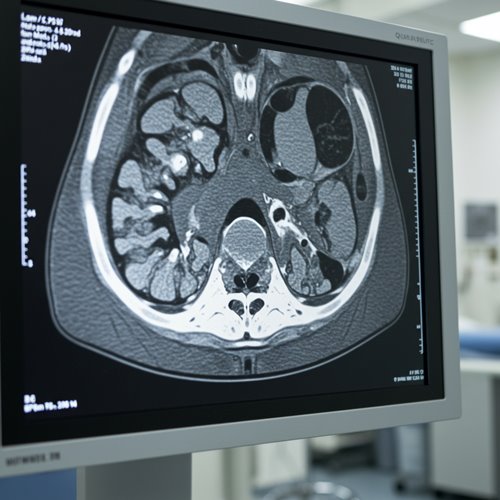

- 영상 검사: CT, MRI 등을 통해 암의 크기와 전이 여부를 평가합니다.